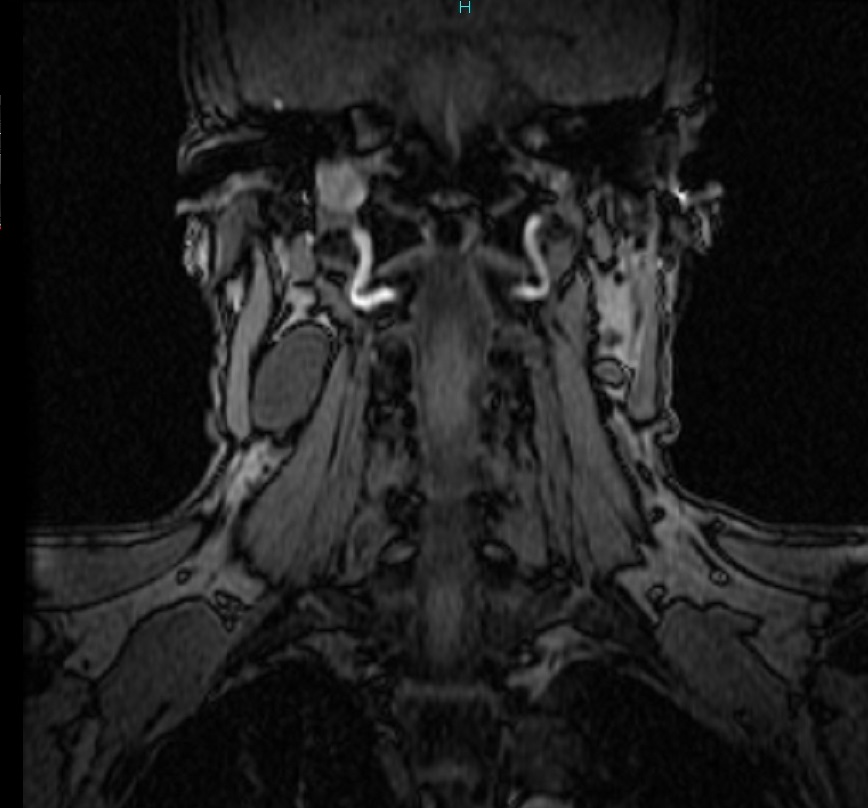

Thyroglossal duct cysts. Neck MRI – Detailed imaging of the cyst. Courtesy Dr. V. Penopoulos.